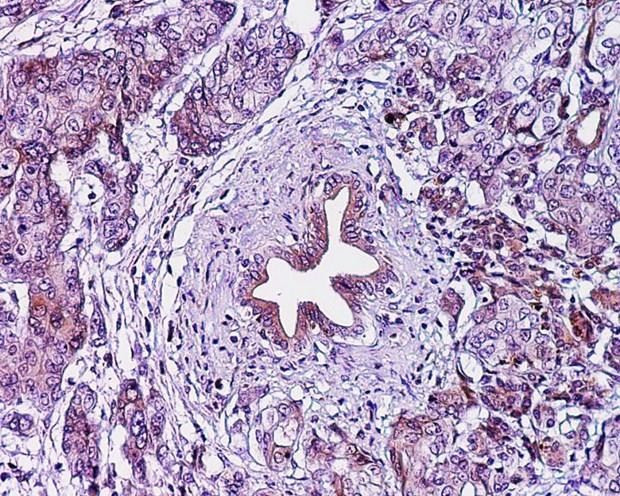

Tìm ra phương pháp giúp ngăn ngừa sự tiến triển của ung thư tuyến tụy ảnh 1Lớp cắt biểu bì ung thư tuyến tụy. (Nguồn: eurekalert.org)